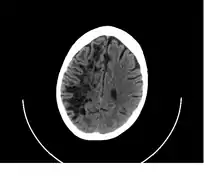

A perivascular space as seen on CT